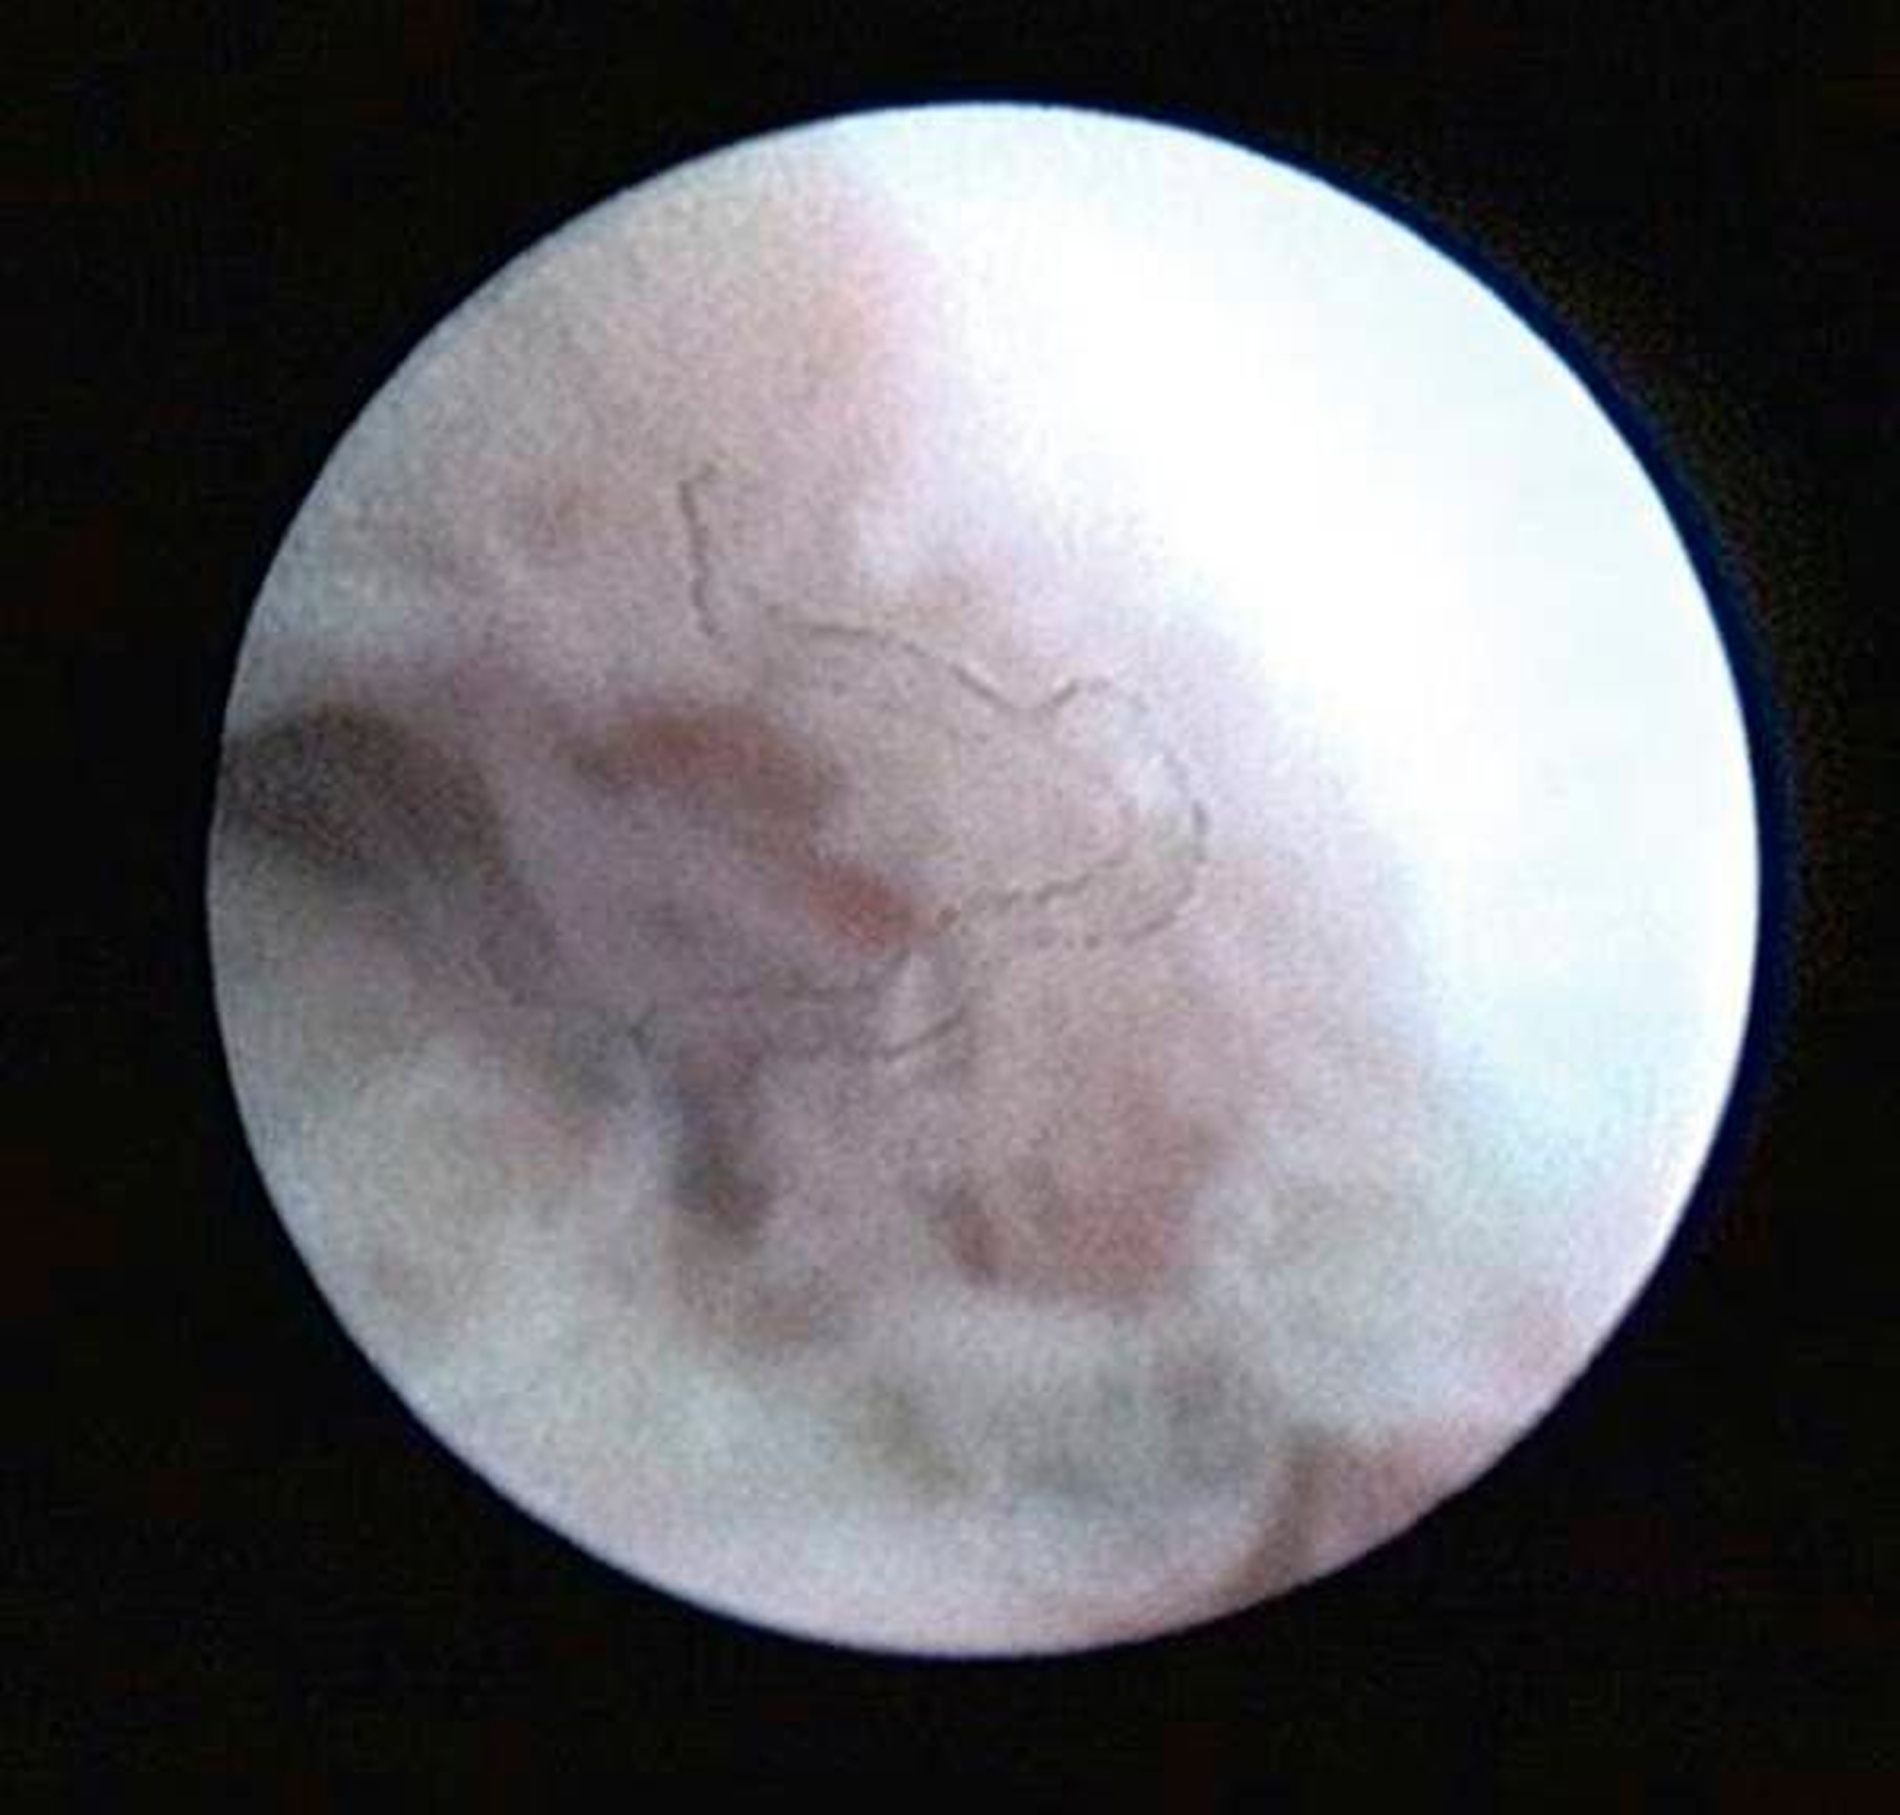

Die Kiefergelenksdestruktion wird als Ergebnis eines katabolen Prozesses verstanden, der die regenerativen Fähigkeiten des Gelenks überlagert und unter anderem durch eine kaskadenartige Aktivierung von Zytokinen vermittelt wird. Dabei kommt es neben einem Verstärkungseffekt durch die Synovial- und Gefäßproliferation zu einer Aktivierung von Osteoblasten. Zytokin-aktivierte Osteoblasten fördern die Rekrutierung und Aktivität von Osteoklasten, diese sezernieren wiederum Enzyme wie beispielsweise Matrix-Metalloproteasen (MMPs), die für den Abbau der extrazellulären Matrix (Hydroxylapatit und Kollagen) des Gelenks verantwortlich sind [Gunson et al., 2011; Zhang et al., 2016; Wang et al., 2012: Ge et al., 2011]. Die Schädigung des Gelenkknorpels wird dabei als „Chondromalazie“ bezeichnet und bei der arthroskopischen Diagnostik je nach Schweregrad im Stadium der Erweichung (Stadium 1), Furchung (Stadium 2), Fibrillation beziehungsweise Fransenbildung (Stadium 3) oder mit subchondraler Knochenexposition (Stadium 4) vorgefunden (Abbildungen 1 bis 3) [Quinn, 1989; Thomas et al., 1991].

Arthroskopisch existieren verschiedene Klassifikationen der Synoviitis, die im Wesentlichen das Ausmaß der beobachteten Gefäßproliferation und Hyperämie berücksichtigt (Abbildungen 4 bis 6) [Mc Cain et al., 1989; Gynther et al.,1994].

Die Kiefergelenksarthroskopie bietet bei gleichzeitiger Lavage eine überragende visuelle Diagnostik des oberen Gelenkraums (Abbildungen 1 bis 7, 13 und 14).

Zur Planung eines arthroskopischen Eingriffs am Kiefergelenk sollte ein möglichst aktuelles MRT der Kiefergelenke vorliegen, sofern hierfür keine Kontraindikationen bestehen. Dabei ist zu beachten, dass radioogisch diagnostizierte Pathologien durch die MRT nicht zwingend voraussetzend für eine Kiefergelenksarthroskopie sind. Bei Patienten mit symptomatischen Kiefergelenkschmerzen, aber radiologisch okkulten Kiefergelenksentzündungen ist die Kiefergelenksarthroskopie bislang immer noch das einzig relevante Verfahren zur Sicherung der Diagnose (Abbildungen 4 bis 6).